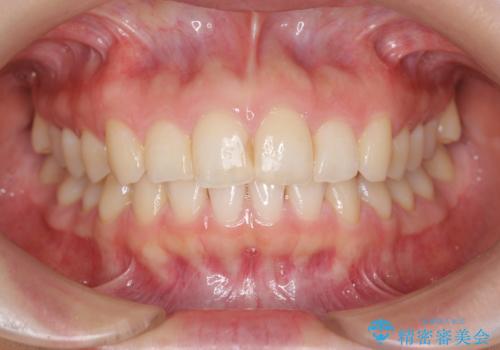

出っ歯に見える前歯の改善 部分ワイヤーとマウスピース矯正

- 出っ歯に見える前歯の改善を希望され、来院されました。

マウスピースでは改善の難しい歯の動きを部分ワイヤー矯正で整えたのち、奥歯の噛み合わせや細かい歯の並びをマウスピース矯正インビザラインで整えていきます。

最終的な前歯の並びに大変満足いただくことができました。